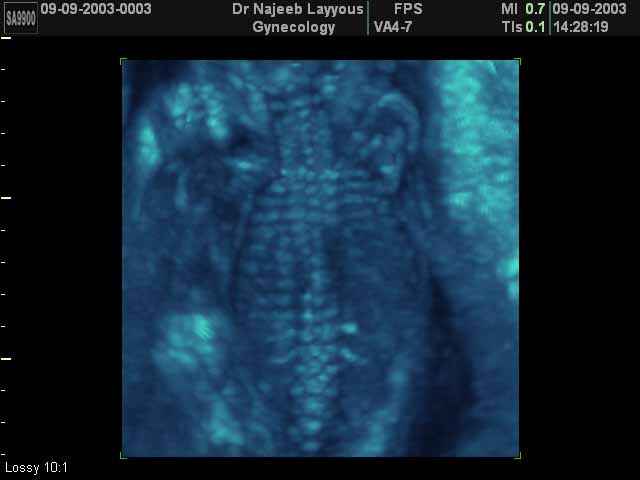

- صور للهيكل العظمي للجنين

صور للهيكل العظمي للجنين بجهاز الالتراساوند ثلاثي الأبعاد | الدكتور نجيب ليوس